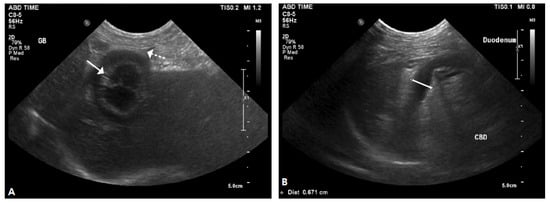

2.2. Case II